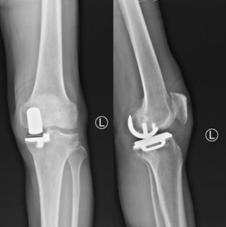

团队为潘阿姨实施了右膝关节单髁置换术,手术时间50分钟不到,手术中无需输血。术后24小时内,潘阿姨就可以在助行器帮助下下地行走,术后没有疼痛。

(潘阿姨手术后X线片)